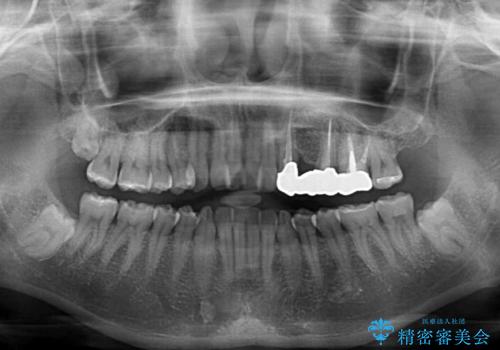

捻れた前歯と銀歯のブリッジを治したい ワイヤー矯正とオールセラミックブリッジ

- 上下前歯のデコボコと銀歯のブリッジを気にして来院された患者様です。

装着されているブリッジを切断して矯正治療を行うことや、手間をかけずに早めに治療を終えたいとのことで、目立たないワイヤー装置による矯正治療を行うこととしました。

矯正治療後には切断したブリッジをオールセラミックブリッジに置き換えることとしました。